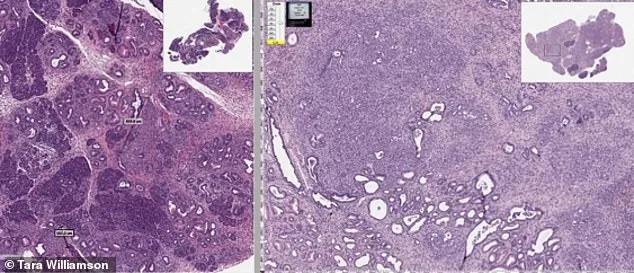

Mebendazole, a drug originally developed to combat parasitic infections like pinworm and whipworm, has been used safely for over 40 years. Yet, recent research hints that its molecular structure might also hold the power to starve cancer cells. Laboratory studies described in the patent show that a particular form of the drug—known as polymorph C—could be more effective at dissolving tumors. One experiment on mice with brain tumors found that those treated with the drug lived significantly longer than untreated controls. The implications are staggering: a medication already in use worldwide could be repurposed to fight some of the most aggressive cancers.

The patent also suggests that mebendazole might not just treat cancer but prevent it. For people at high risk—such as those with genetic predispositions to colorectal cancer—the drug could act as a preventive measure. This raises ethical questions: Should such a drug be made widely available, even if it means challenging the billion-dollar cancer drug industry? Or is the research still in its infancy, requiring years of trials before it can be trusted?